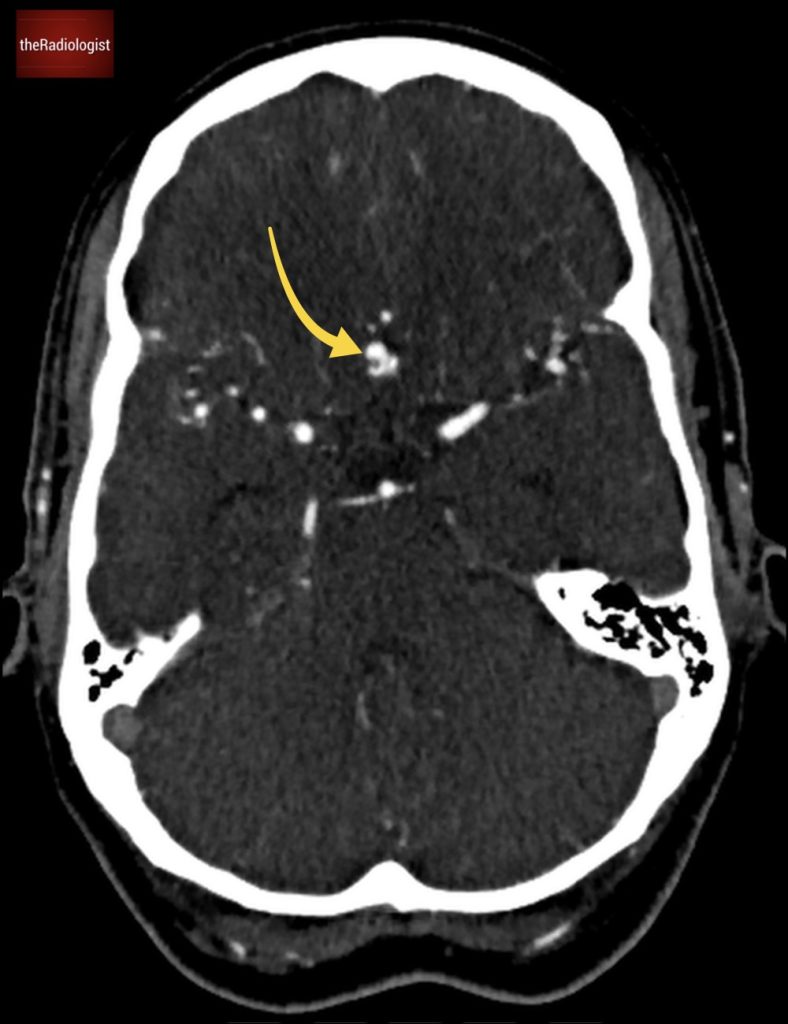

On a follow up MRI scan 2 months later we can see the right psoas is now returning to normal.

The patient was treated with a long course of antibiotics and we saw a good response on imaging with improvement in the right psoas abnormality at 2 months.